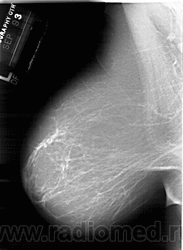

Со старением железистая ткань постепенно исчезает: прозрачность жировой ткани становится преобладающей с несколькими каркасами, связанными с опорными волокнистыми структурами.

Жирная (не плотная) грудь

Умеренно плотная грудь

Плотная грудь

Маммограммы представляют собой изображения структур, проецируемых на плоскость: плотная грудная маммограмма, следовательно, состоит из многих других структур, которые необходимо проанализировать, чем более жирная, пустая грудь. По этой причине диагностировать рак молочной железы труднее для моложе, чем для пожилых женщин.

Нажмите на миниатюрные картинки, чтобы получить увеличенный размер.